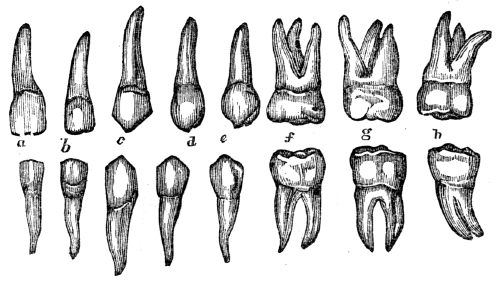

| 12. | Anatomy of the Teeth, | 105 |

| 12. | Physiology of the Teeth, | 109 |

| 12. | Hygiene of the Teeth, | 110 |